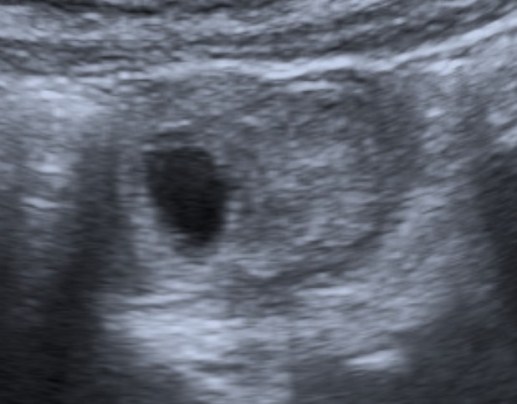

Se realiza ecografía de abdomen. Se observa:

En la evaluación ecográfica se puede identificarse una estructura tubular que termina en saco ciego con contenido líquido, en el borde antimesentérico del íleon terminal,

localizada a nivel abdominal en cuadrante inferior derecho. Estos hallazgos han provocado que se diagnostiquen erróneamente como apendicitis cuadro de diverticulitis de Meckel, sin bien la actitud terpéutica (que suele ser la cirugía) no varía.

Puede observarse también como una estructura quística con paredes que recuerdan asas intestinales: banda hiperecoica que correspondería a la mucosa y otra banda hipoecoica que correspondería a la muscular. Han sido confundidos con quístes de duplicación (los cuales tienen sin embargo márgenes más regulares). La señal Doppler color puede muestran hiperemia como signo de inflamación del diverticulo.

Recordar que pueden econtrarse enterolitos en el interior del divertículo e incluso gas, el cual puede confundirnos con un asa intestinal (usar transductores de alta frecuencia).